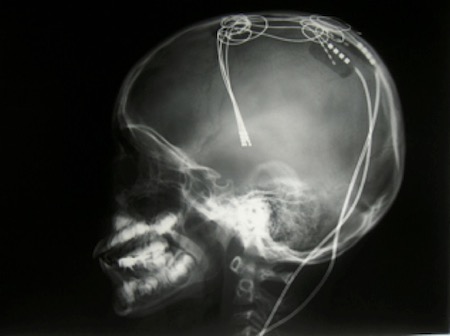

脳深部刺激療法(DBS)は、脳の深部にある特定の領域に電極を埋め込み、体内に埋め込んだ刺激装置から電気刺激を与えて、パーキンソン病、本態性振戦、ジストニアなどの症状を改善する治療法である。飲み薬の効果が不十分な場合に適用され、脳の異常な活動を抑制することで、症状の緩和を目指す。

パーキンソン病に対する脳深部刺激療法(DBS)などでは、電極を埋め込む際に患者に楽器を演奏してもらい、症状がどれだけ改善するかをその場で調整する。